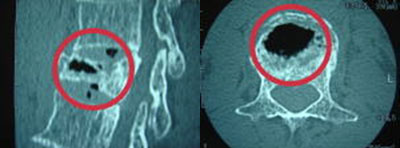

椎体形成術

椎体形成術とは、椎骨の骨折である脊椎圧迫骨折(VCF)の治療として行われる手術で、お体への負担を抑えて手術することが可能です。

保存療法では症状の改善が見込めない場合などに、全身麻酔下で小切開で手術できます。

BKP手術内容

不安定性があり、骨癒合が得られていない脊椎椎体骨折に対し、骨セメントを注入する手術。

BKP術式

術前

骨癒合が得られておらず、椎体内に空間があります。

CT

CT

術後

空間にセメントが詰められています。

CT

CT